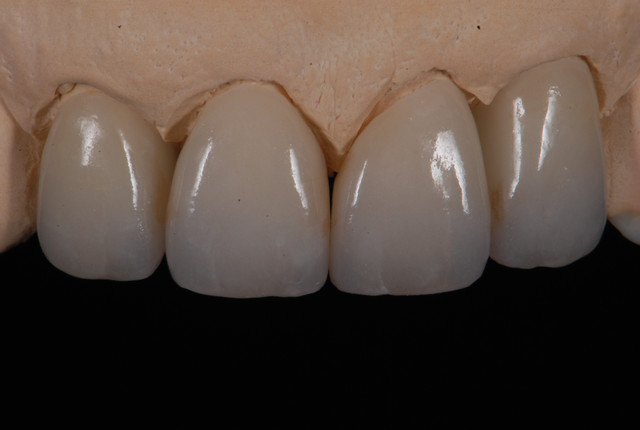

E.max crown try in 280713

#Togias 190713 nora